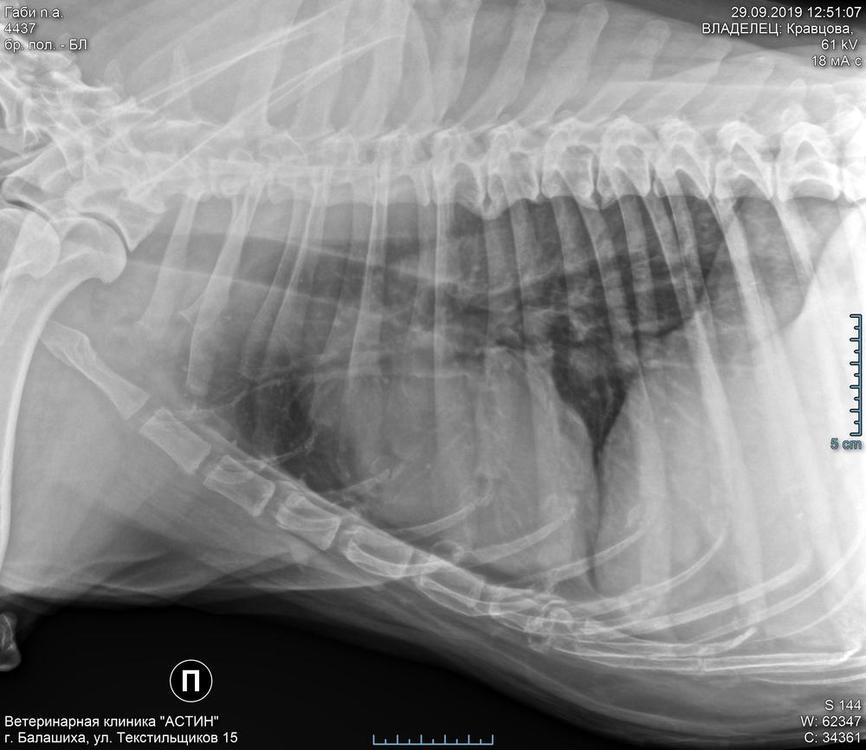

Лера&Чили Опубликовано 29 сентября, 2019 Опубликовано 29 сентября, 2019 Габушка с Леной сегодня приезжали на обследование и консультацию онколога . По результатам : диагноз - рак молочной железы. Рентген грудной клетки , узи брюшной полости метастаз не показали . Но на снимке доктор указал на два участка , к которым есть вопросы , на которые ответить можно лишь после более точного обследования ( КТ) . Доктор сказал что новообразование удалять необходимо , операцию нужно проводить в ближайшие сроки ( потому что результаты обследования корректны в течении небольшого промежутка времени , в дальнейшем ситуация может довольно быстро изменится , не известно насколько быстро новообразование будет расти и как будет реагировать организм , тем более в Габушкиной ситуации ) . На КТ попасть сегодня , к сожалению , не удалось - не было свободного « окна « . Из назначенных обследований сделали УЗИ сердца - по результатам никаких отклонений / вопросов / противопоказаний к операции нет . и немножко о Габусе .. трогательная , милая , такая стойкая , терпеливая , все манипуляции и обследования вынесла очень достойно ,....и такая беззащитная , растерянная когда рядом нет Лены . Лена для Габуси « весь мир « . Только рядом с ней она спокойна и уверенна , только рядом с ней она готова ко всему .. Габуся не видит уже давно , и она давно уже научилась жить с этим , но теперь у неё снизился слух практичеки совсем , и с этим ей гораздо сложнее адаптироваться . Она не может теперь ориентироваться на слух , не может распознавать и анализировать происходящее вокруг , и только , почувствовав что рядом ее любимая Лена , она знает точно , что ничего плохого с ней не случится , она под надежной защитой , и если надо потерпеть значить надо , главное что Лена рядом . И ещё , я очень - очень верю что Габуся у нас везунчик , не смотря ни на что, ни на какие ее проблемы и болячки ! Она столько раз уже доказывала что главное это любовь , главное что ты нужна , а для Лены Габуся это отдельный мир.. Лена делала и сделает всё что бы преодолеть очередную напасть !! И у Габушки всё будет хорошо !! Обязательно ! Девочки , вы замечательные , удивительные , у вас такая , особенная , связь друг с другом !! Я вас очень люблю ! Прорвёмся обязательно !!